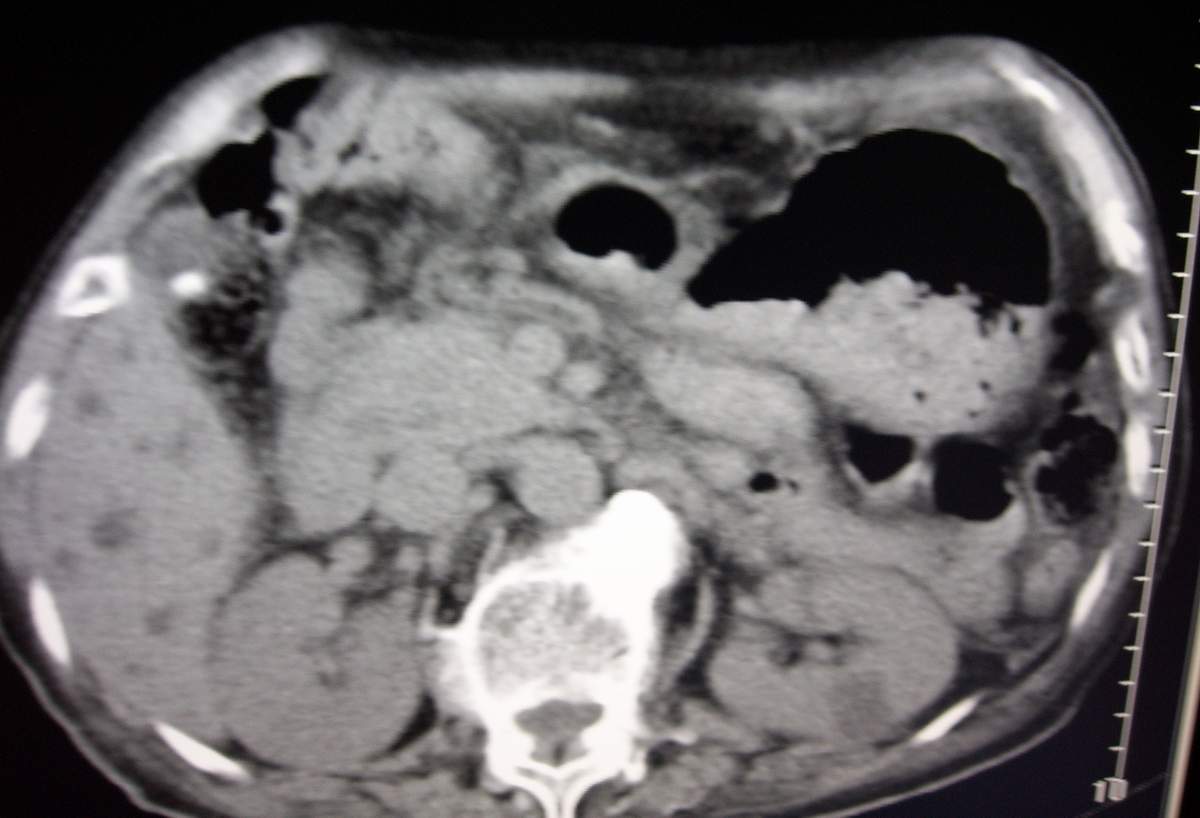

男,77岁,病史不详。

肝内胆管扩张、主胰管扩张 ,胰头影大,考虑胰头癌或胆管下端癌侵犯胰腺可能性大

慢性胆囊炎,胆结石,左肾囊肿,胰头癌伴肝内胆管、胰管扩张,不除外侵犯肠系膜上静脉的可能。

肝内外胆管明显扩张,肝门区见软组织密度肿块,胆囊壁增厚,胆囊扩大。胰头不大。考虑:肝门区胆管细胞癌。

1肝门区域软组织影,肝内胆管明显扩张,胰管轻度扩张。考虑肝门区胆管细胞癌。2胆囊结石。3左肾小囊肿。

1 肝内外胆管扩张,肝内明显,胰管扩张,胰头明显增大,符合胰头癌双管征。2 胆囊壁略增厚,胆囊内可见高密度结石影,胆囊炎、胆结石3 左肾囊肿

左肾小囊肿;胆囊结石、胆囊炎;肝内外胆管明显扩张;胰管增宽[炎性病变所致]。